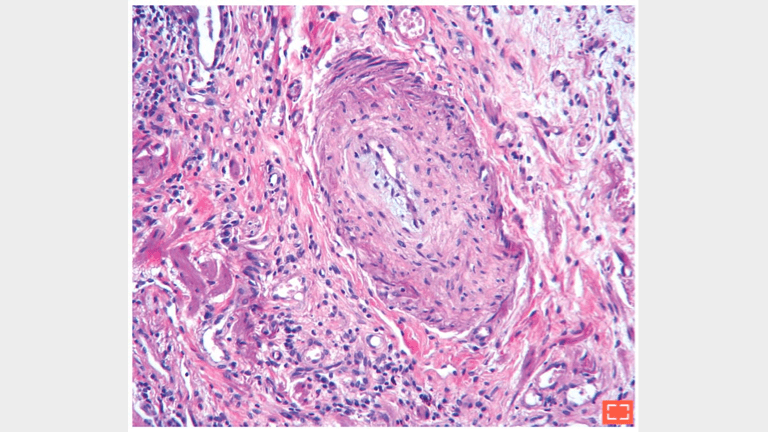

• Marked intimal and medial hyperplasia in this artery

Hypertensive arterial lesion.

Reduction of the vascular lumen in fibrotic area.